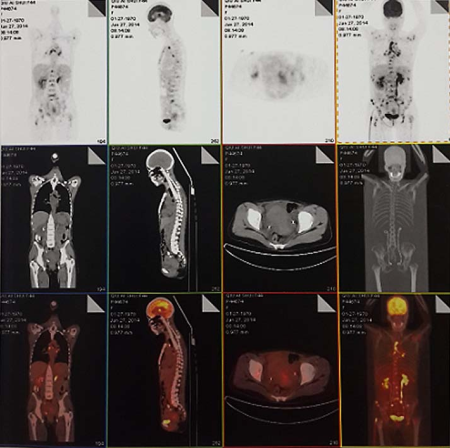

确诊后根据具体情况选择胸部X线或CT平扫、静脉肾盂造影、膀胱镜检査、直肠镜检查、超声检查及盆腔或腹腔增强CT或磁共振、PET-CT等影像学检查。

子宫颈癌全身广泛转移PET-CT